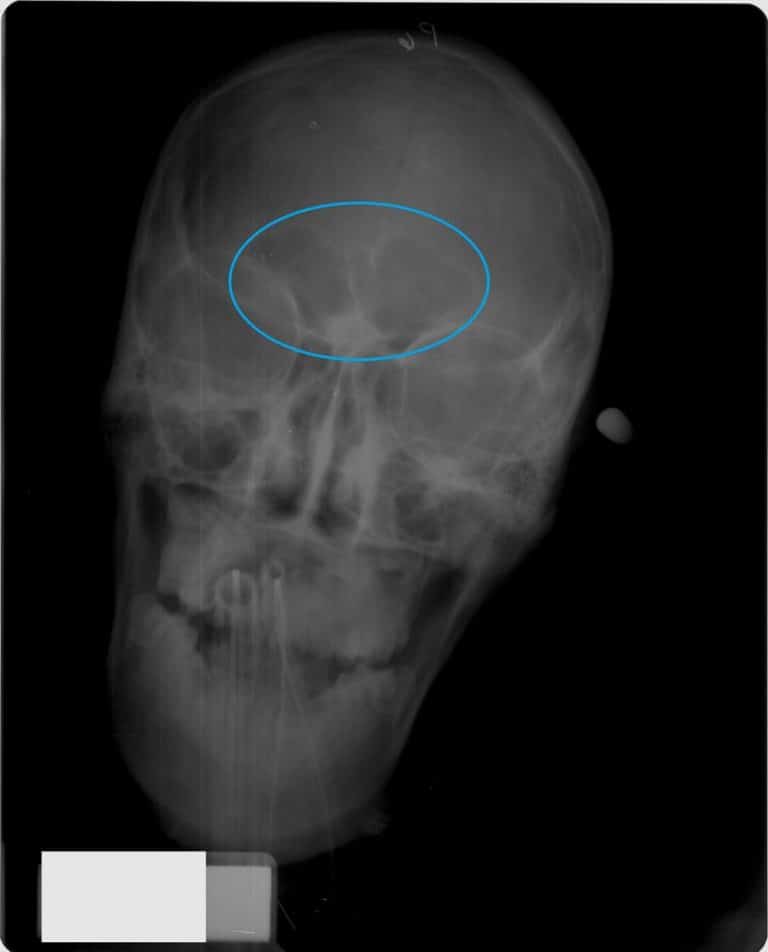

وفي الدراسة التي أجرتها روس وزميلتها كايتلين مور، ونُشرت في مجلة السجل التشريحي يوم الثلاثاء الماضي، تصف الباحثتان مراحل تطور الجيب الجبهي بالتزامن مع نمو الجمجمة. وخلافاً للجيوب الأخرى الموجودة في الوجه (مثل الجيوب الأنفية) فإن الجيب الجبهي يبدأ بالتطور في عمر سنتين، ولا يظهر على صور الأشعة السينية إلا بعد تجاوز الطفل لعمر 6 سنوات.

وقد تمكنت الباحثتان من تمييز أربع مراحل من تطور الجيوب الجبهية، وذلك عن طريق مقارنة 392 صورة بالأشعة السينية لجماجم أطفال، وهي:

- مرحلة عمر 6 سنوات أو أقل، حيث لا تظهر أية جيوب جبهية.

- مرحلة ما بين 6-8 سنوات، حيث تتطور لدى الطفل جيوب جبهية بحجم حبة الفول في مقدمة الرأس.

- مرحلة ما بين 7-10 سنوات، حيث يأخذ الجيبان الجبهيان بالاتساع إلى أن يتماسا مع بعضهما.

- مرحلة ما بين 12-18 سنة، حيث تتشكل الجيوب الأنفية بشكل كامل.